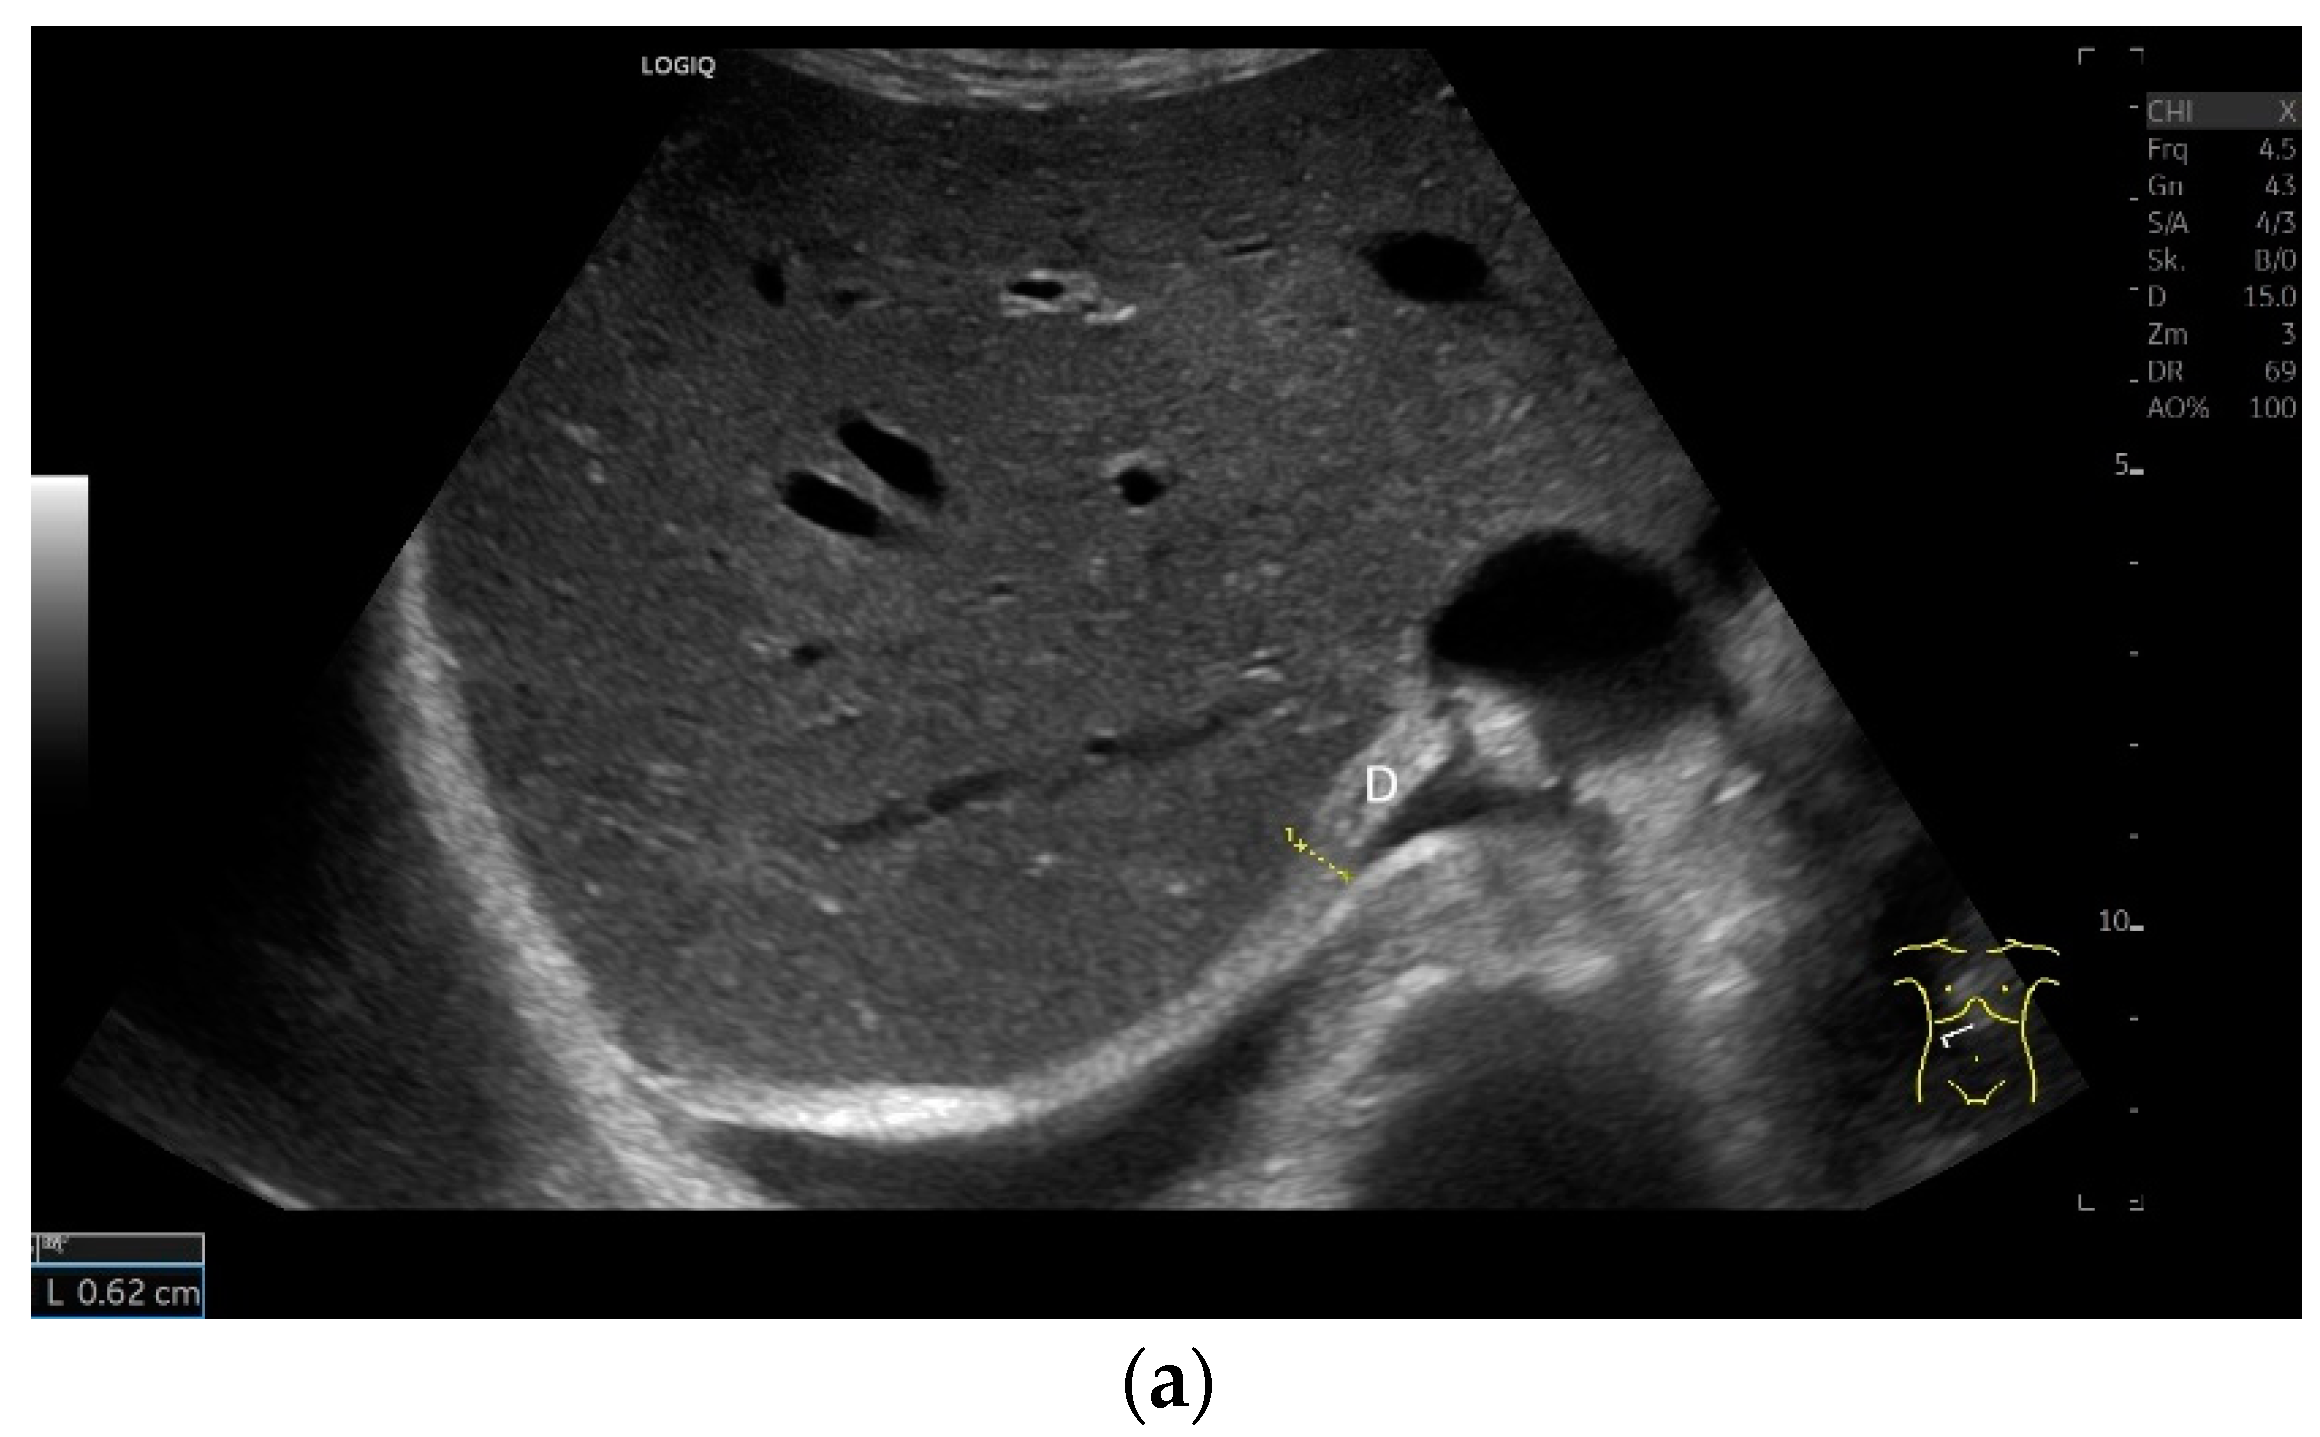

Subxiphoid: The diaphragm can be positioned directly subxiphoidally with a slightly sagittal transducer position on both sides next to the attachment to the sternum. The diaphragm limb can be demarcated to the right in the epigastrium in cross section between the aorta and the inferior vena cava. However, this is primarily of differential diagnostic importance, e.g., in relation to lymphomas, not for the actual assessment of the diaphragm (Figure 6).

Regardless of the recommended positions for standardized measurements, the diaphragm can be viewed in other areas. This works quite well on the flank and subcostally in the midclavicular line (Figure 7).